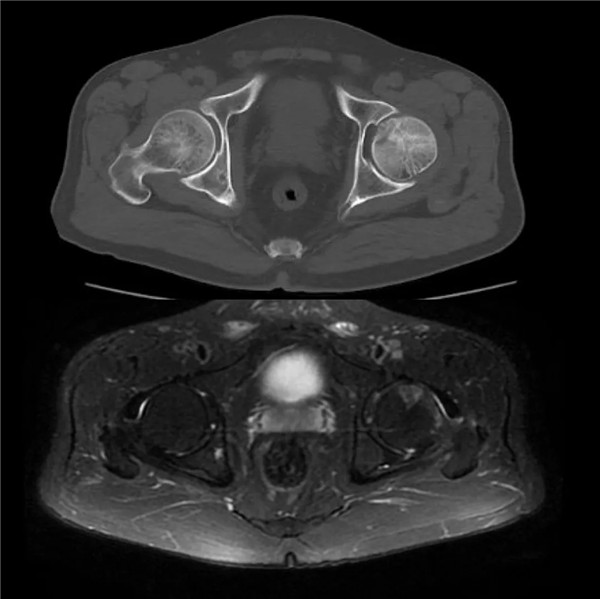

(CT和磁共振顯示:髖關(guān)節(jié)撞擊征合并股骨頭壞死)

經(jīng)查體及拍片檢查后,副院長(zhǎng)危立軍診斷為“髖關(guān)節(jié)撞擊綜合征合并股骨頭壞死”,建議其入院,并接受手術(shù)治療。

當(dāng)天上午,余大伯入住我院關(guān)節(jié)科病區(qū)。廣安骨科中心副主任、關(guān)節(jié)科主任羅軍在查體時(shí)進(jìn)一步確診為股骨髖臼撞擊綜合征、股骨頭壞死早期,建議開(kāi)展關(guān)節(jié)鏡微創(chuàng)手術(shù)治療。在與家人商量后,余大伯決定手術(shù)。